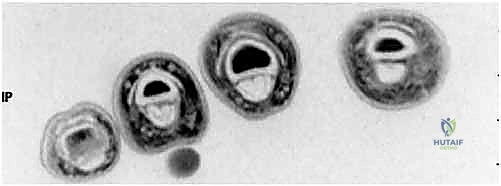

- FDP Avulsion (Jersey Finger): A lateral radiograph can reveal a bony fragment caught at the A4 pulley, indicating the level of tendon retraction.

FIG 2 • A. Flexor digitorum profundus (FDP) avulsion in which a bony fragment has been caught up at the A4 pulley.

FIG 2 • C. Axial cut MRI at the level of the proximal phalanx shows both FDP and flexor digitorum superficialis (FDS) tendons are present. D. At the level of the middle phalanx, only the FDS tendon can be seen.

FIG 2 • B. Lateral radiograph of a finger demonstrates chronic dorsal dislocation of the DIP joint, with associated arthrosis.